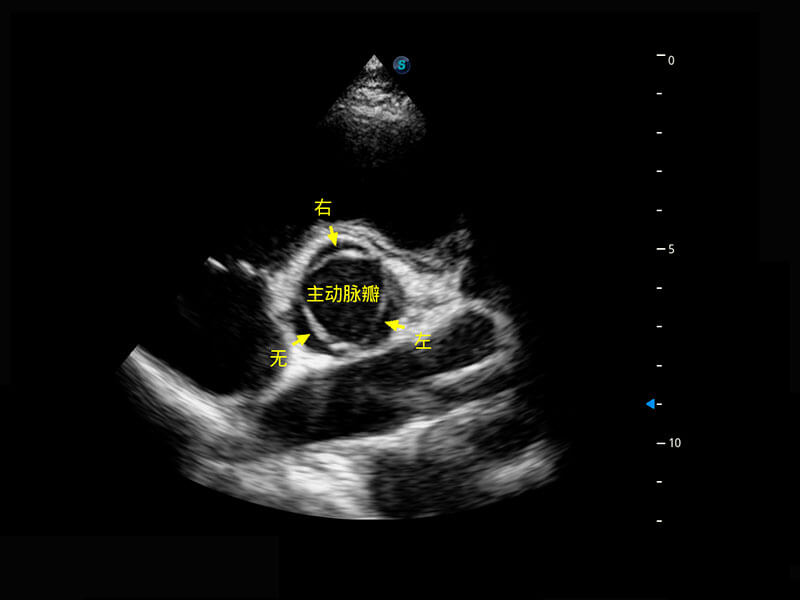

胎心筛查

P60搭载一系列胎儿心脏成像技术,实现精细的胎儿心脏评估。

• 右室双出口